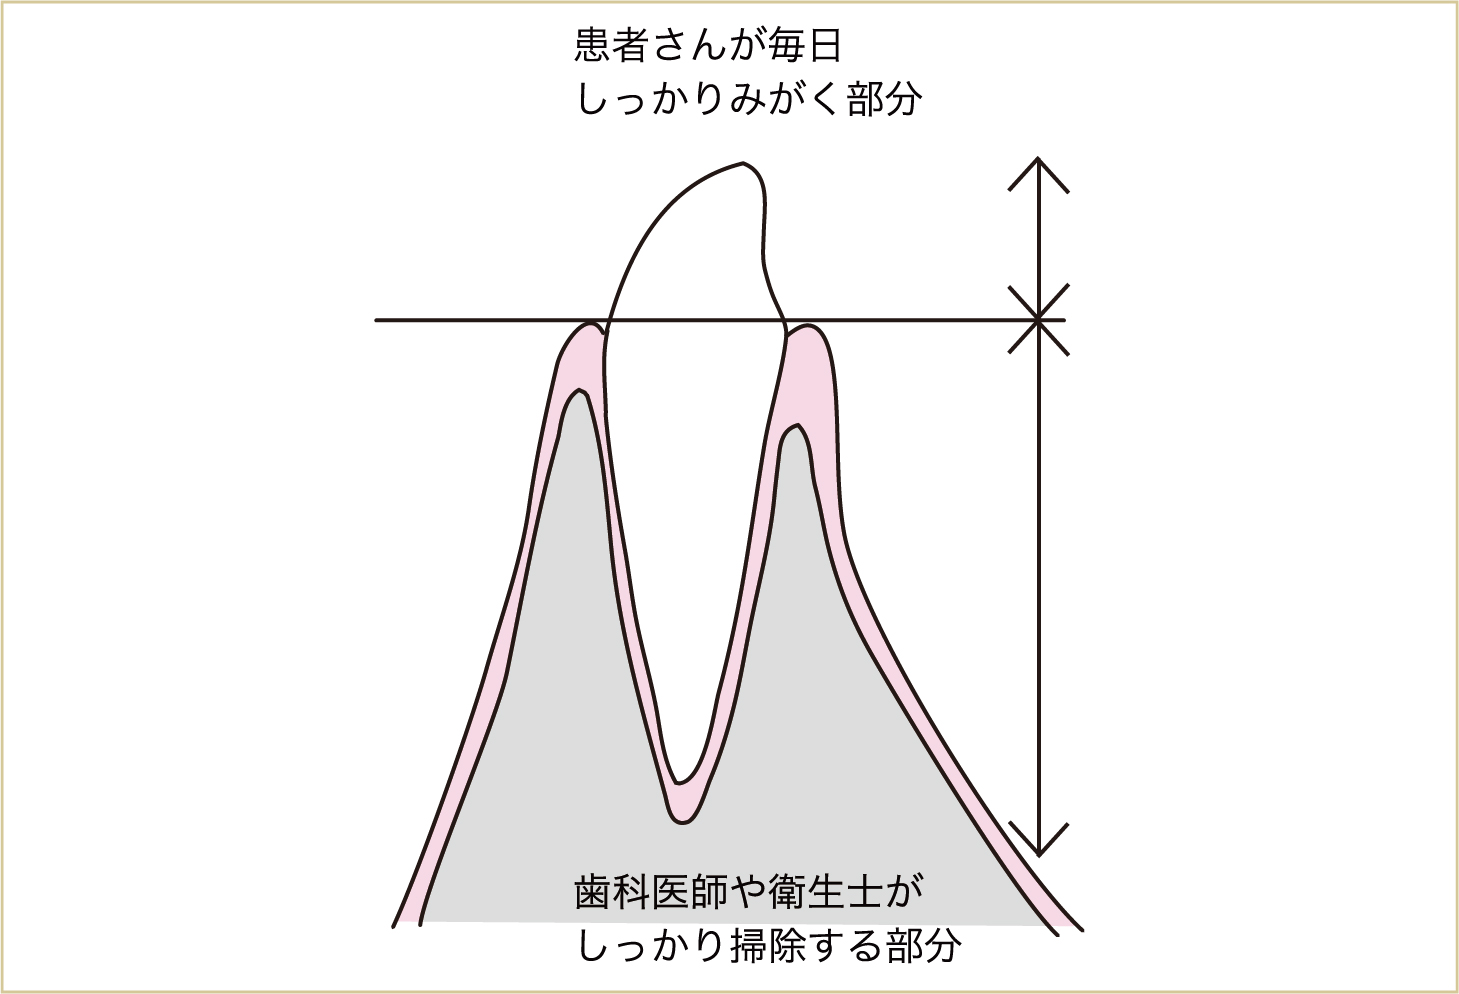

歯肉の中に侵入してきた毒素や細菌は、歯ブラシではとることができません。ですから、歯肉の中に存在する汚れや歯石は、麻酔をかけるなどして専門家である歯科医師や歯科衛生士にとってもらうことが大切です。

一方、歯肉の上の部分についている汚れは、患者さんが毎日みがいてとることが大切で、これは患者さんにしかできないことでもあります。歯周病の予防に最も大切なのは、この最初に降り積もる汚れを、毎日しっかりとみがいて清潔にするということです。なぜなら、骨が壊れた状態になってしまっては、私たち歯科医師や歯科衛生士が歯肉の中の隠れた汚れをとり、歯肉より上の汚れをしっかりとみがいて清潔にしたとしても、壊れた骨を元に戻すことはできないからです。

歯周病の予防・治療には、患者と歯科医療担当者との協力が重要。ブラッシングは患者自身にしかできないし、これに勝る方法はない。

腕の骨折などで折れた所は骨が強くなって治っていきますが、歯周病で壊れた骨は元には戻りません。これは歯周病が、その歯があるせいで身体の中に細菌や毒素が入ってきている、だから身体から歯を外そうとしたもので、自分自身で歯を支える骨を壊しているからです。 つまり、必要に応じて身体が壊したものなので、元には戻らないのです。したがって、歯周病は進行を止めることが第一目標の病気ということになります。だからこそ、骨が壊れる前の初めについた汚れを毎日しっかりときれいにして、歯肉の中まで汚れや歯石がつかないようにしてほしいのです。

歯肉の中に隠れている歯根の汚れや歯石は、専門家にとってもらいましょう。